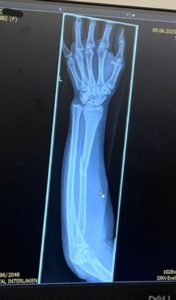

Recently, one of our customers experienced an accident while travelling in Switzerland. Thankfully, she had purchased travel insurance before the trip.

After assessing the situation, the emergency team arranged for helicopter evacuation to send her to the nearest hospital for treatment.

The total claim amount for this case was more than RM120,000, which included:

• Overseas hospital medical expenses

• Helicopter evacuation to hospital

• Follow-up medical treatment after returning to Malaysia

*Claim documents and medical evidence related to the case.

(Some personal information has been removed for privacy.)